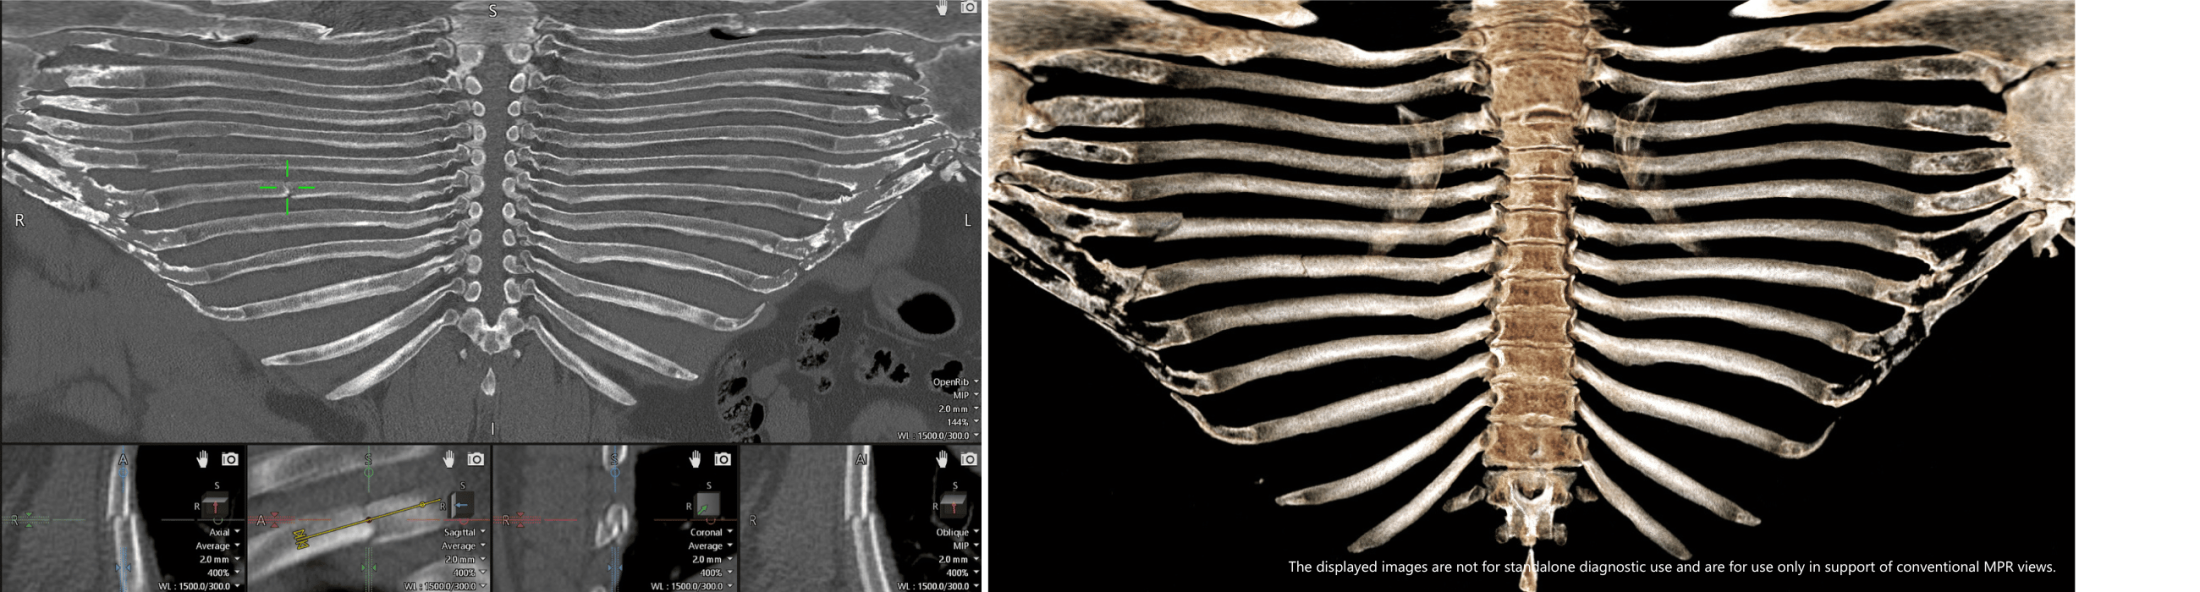

The Open Rib application for Vitrea® Advanced Visualization is image analysis software for chest CT images. The application offers a visualization of the unfolded rib cage that allows a physician to instantly view the full rib anatomy and should be used as an additional view in adjunct to conventional multiplanar reformat views.

- Simultaneous representation of all ribs in a single view.

- Rapid visualization of rib anatomy and fractures, calcified costochondral cartilage and soft tissue.

- Access to the Open Rib advanced visualization (AV) application, if desired, for a more interactive review.